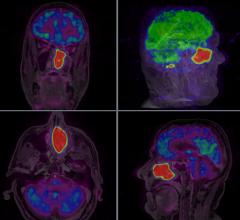

Researchers using magnetic resonance imaging (MRI) have discovered a common pattern of structural abnormalities in the brains of people with depression and social anxiety, according to a study presented at the 2017 annual meeting of the Radiological Society of North America (RSNA), Nov. 26-Dec. 1 in Chicago.